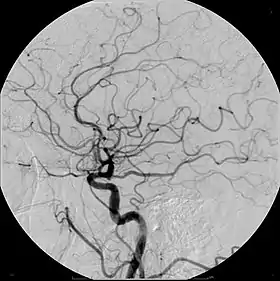

Iodinated contrast contains iodine. It is the main type of radiocontrast used for intravenous administration. Iodine has a particular advantage as a contrast agent for radiography because its innermost electron ("k-shell") binding energy is 33.2 keV, similar to the average energy of x-rays used in diagnostic radiography. When the incident x-ray energy is closer to the k-edge of the atom it encounters, photoelectric absorption is more likely to occur. Its uses include:

- Angiography (arterial investigations)